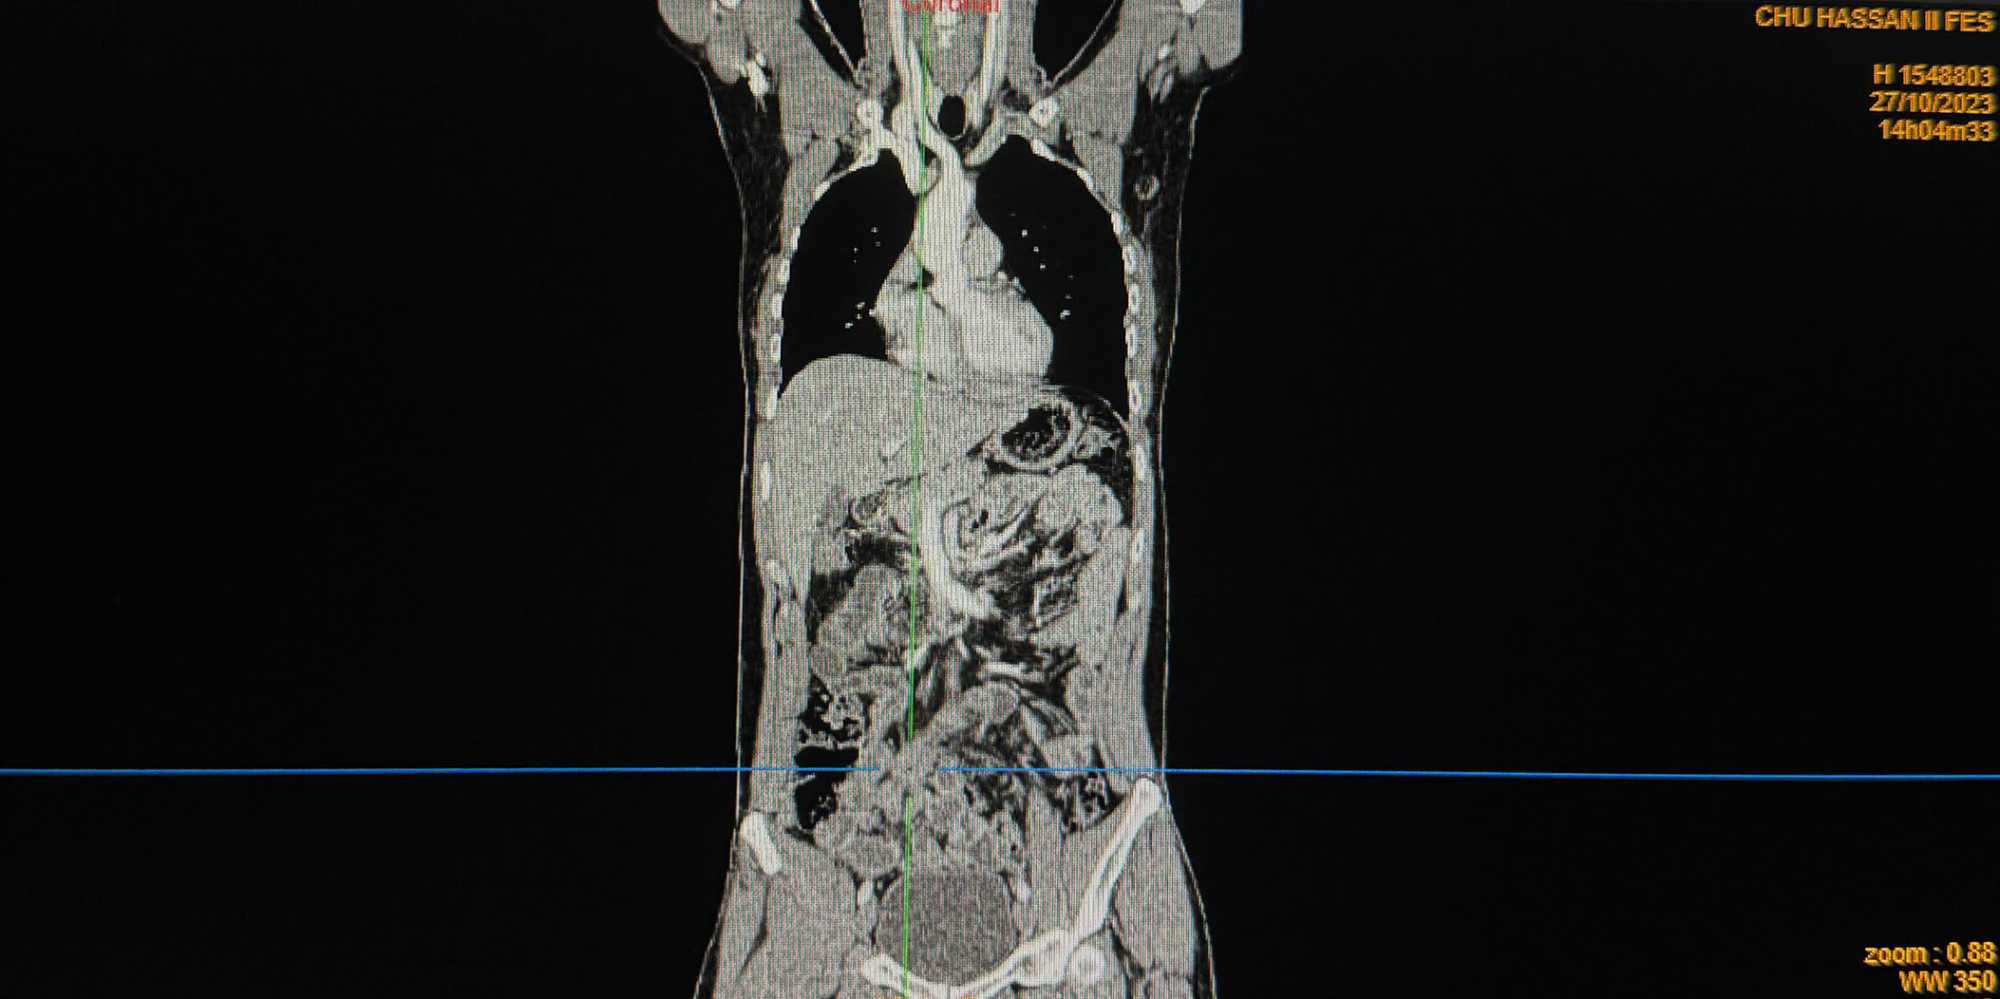

A reassessment CT scan performed on October 27, 2023 (Figures 1-4), after a year of treatment, showed partial regression of the tumor mass measuring then 30 × 18 × 34 mm.

Figure 4. Coronal CT demonstrating tumor reduction following 12 months of sorafenib.